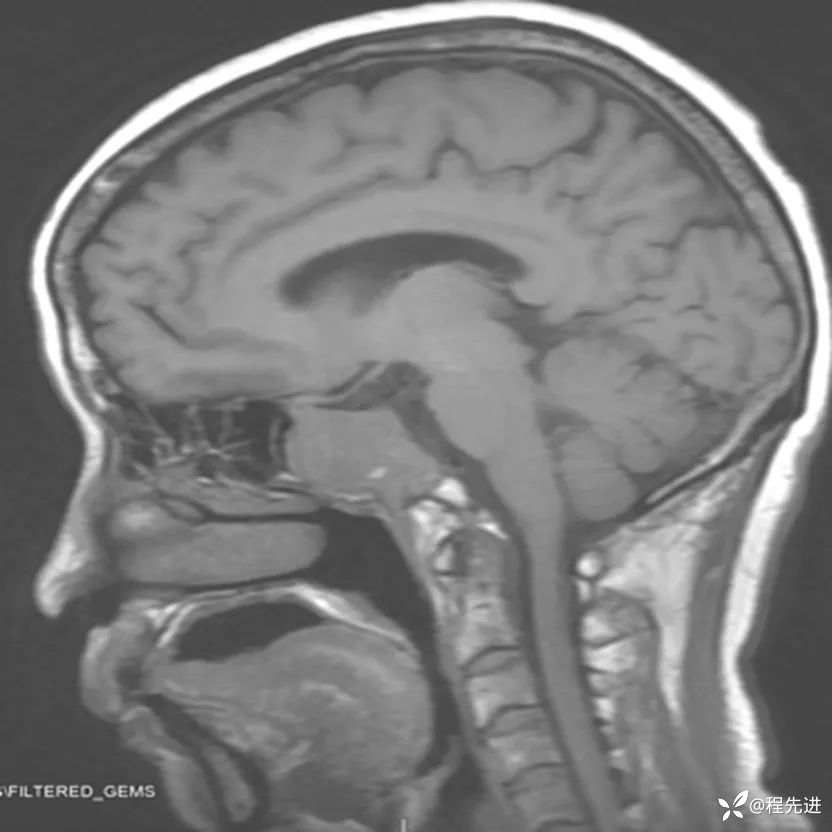

患者性别:女

患者年龄:63岁

简要病史:外伤检查发现颅底占位

MRI平扫+增强: